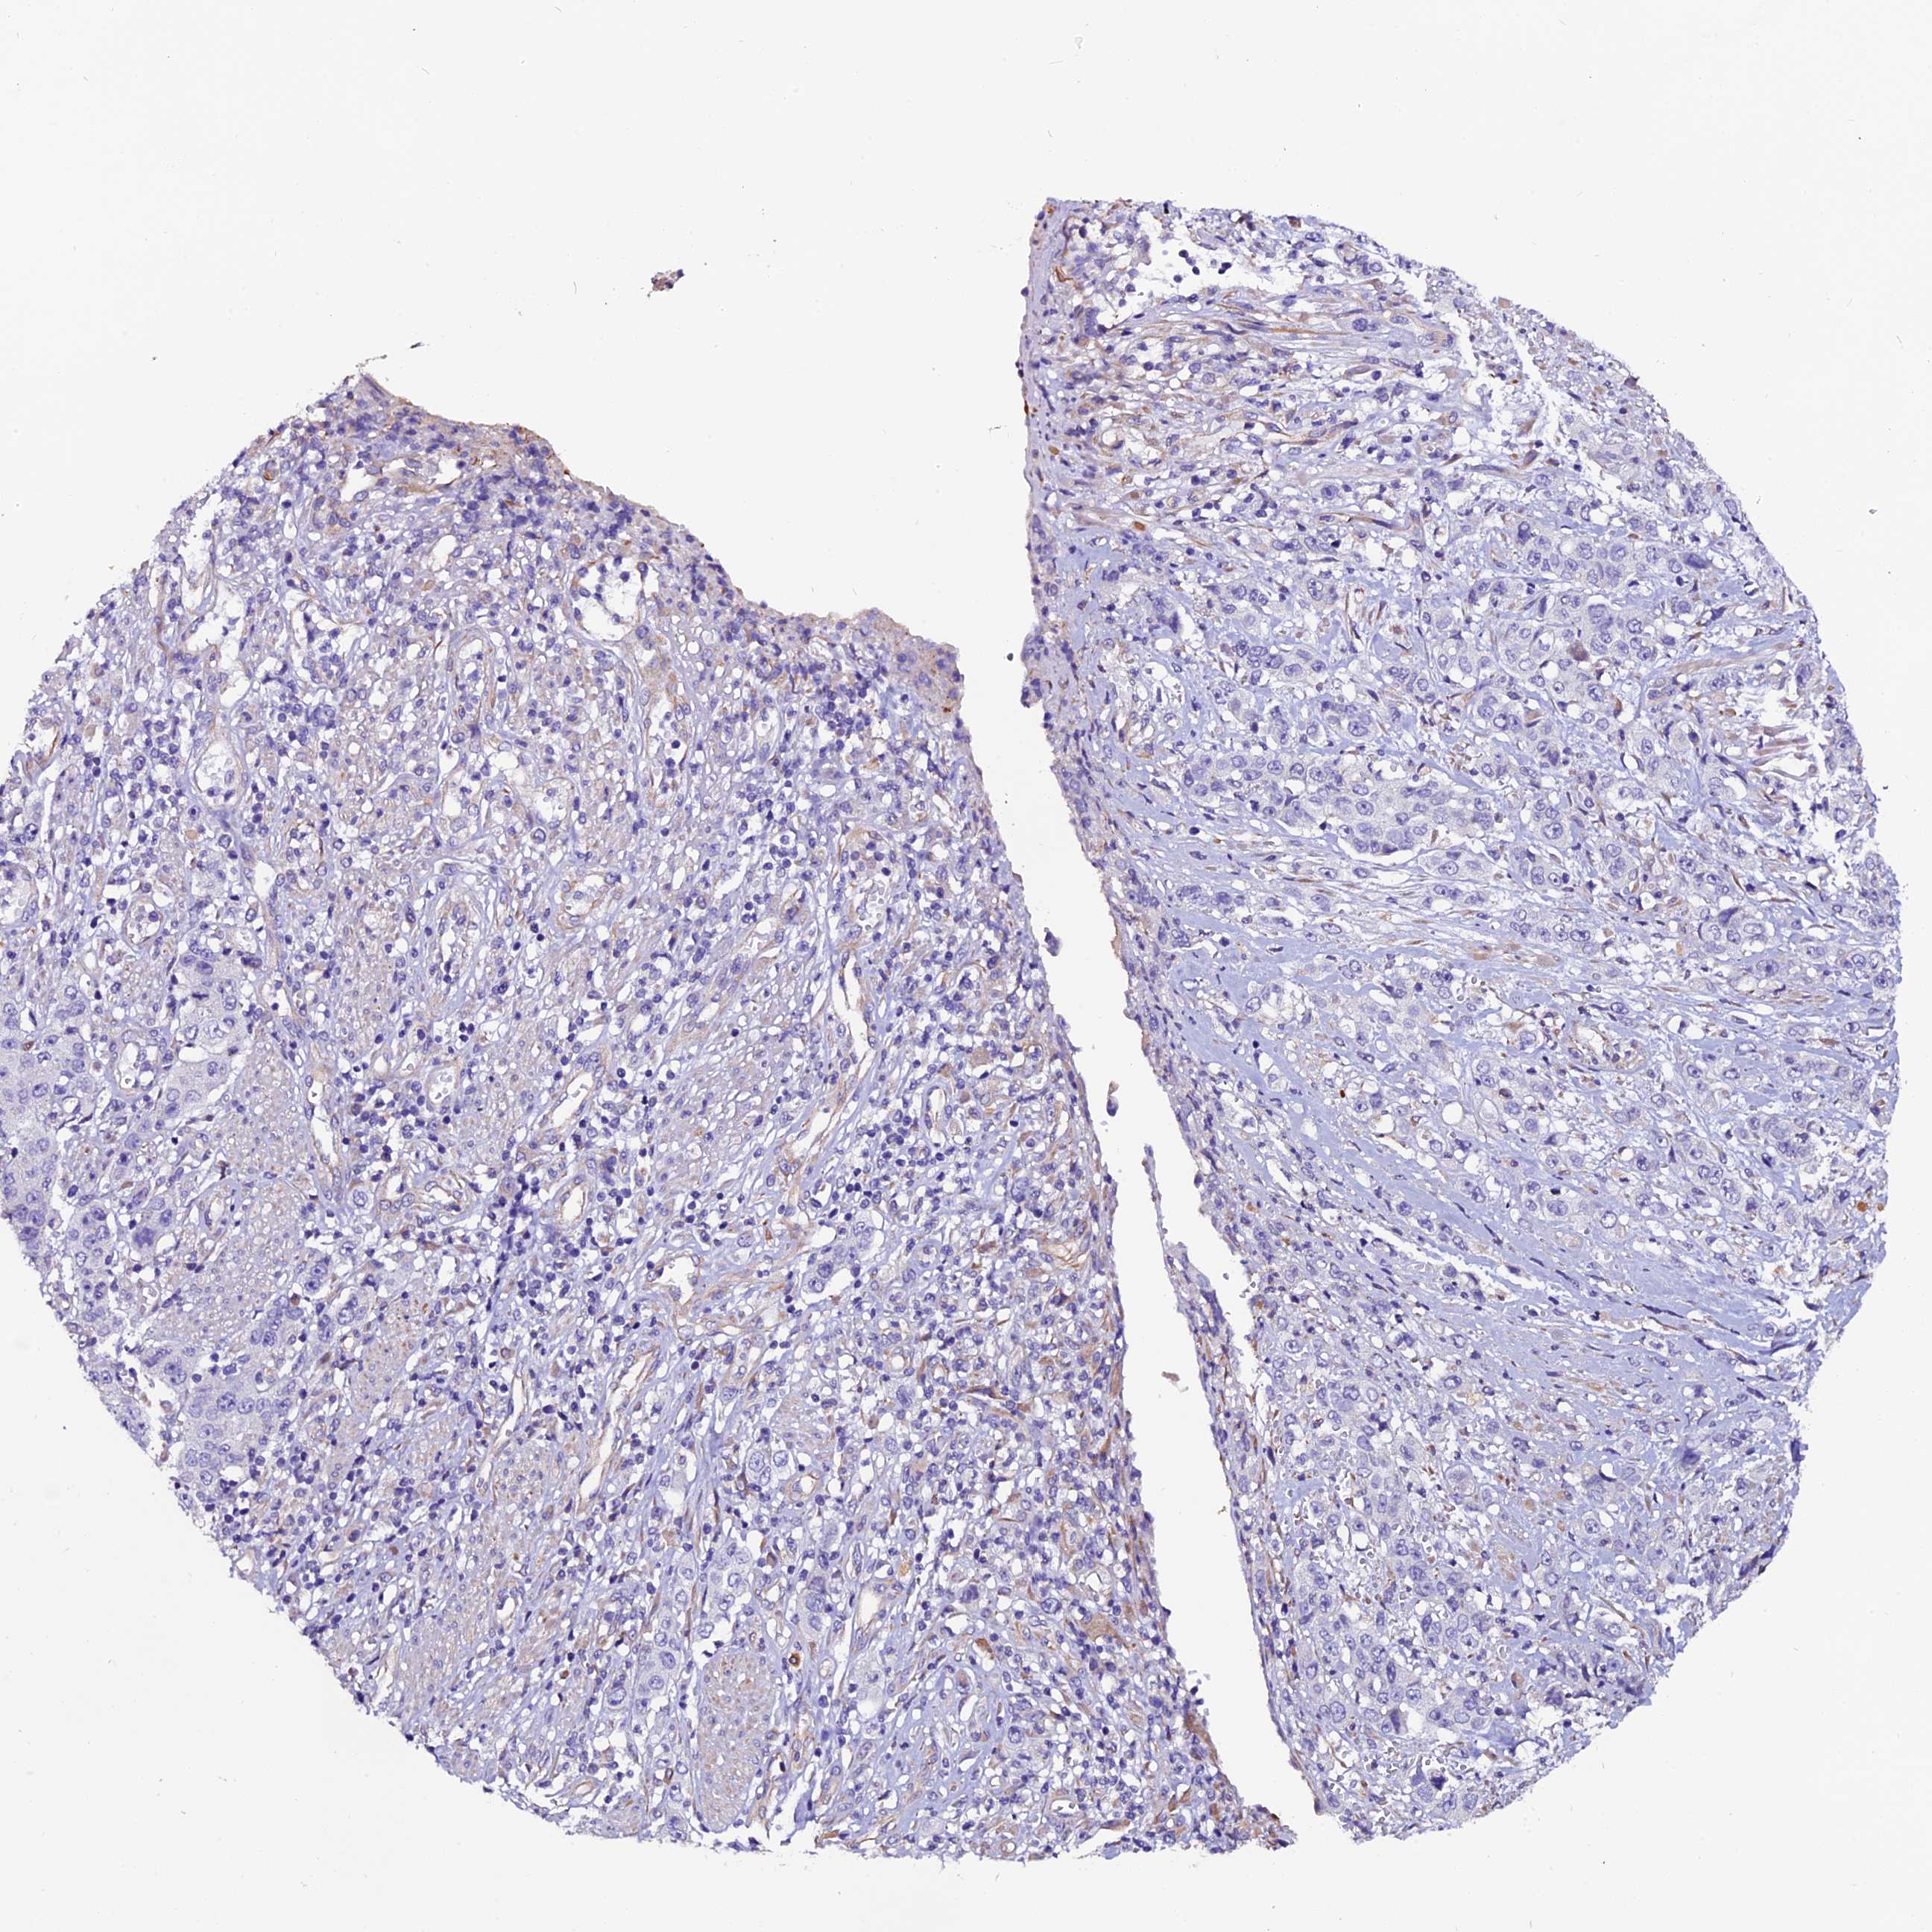

STOMACH CANCER - Protein expressioni

A mouse-over function shows sample information and annotation data. Click on an image to view it in a full screen mode. Samples can be filtered based on level of antibody staining by selecting one or several of the following categories: high, medium, low and not detected. The assay and annotation is described here.

Note that samples used for immunohistochemistry by the Human Protein Atlas do not correspond to samples in the TCGA dataset.

Antibody stainingi

Antibody staining in the annotated cell types in the current human tissue is reported as not detected, low, medium, or high, based on conventional immunohistochemistry profiling in selected tissues. This score is based on the combination of the staining intensity and fraction of stained cells.

Each image is clickable and will lead to virtual microscopy that enables deeper exploration of all samples and also displays staining intensity scores, fraction scores and subcellular localization as well as patient and tissue information for each sample.

Antibody HPA041788

Staining

High

Medium

Low

Not detected

Intensity

Strong

Moderate

Weak

Negative

Quantity

>75%

75%-25%

<25%

None

Location

Nuclear

Cytoplasmic/membranous

Cytoplasmic/membranous,nuclear

Adenocarcinoma, NOS